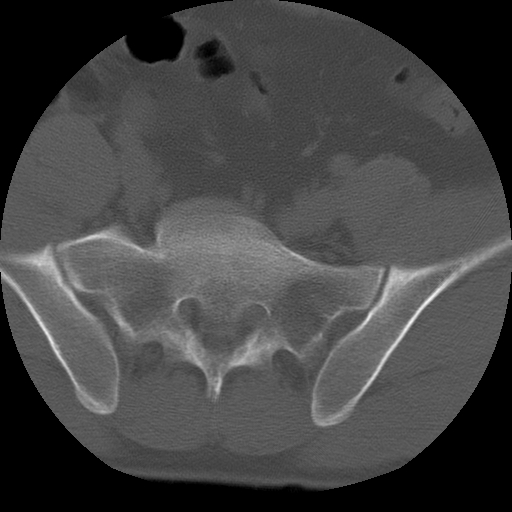

标题: CT24390:男,23岁,腰痛就诊。 [打印本页]

标题: CT24390:男,23岁,腰痛就诊。

男,23岁,腰痛就诊。

腰5右侧横突肥大伴假关节形成.

支持!图像少,再往下扫骶髂关节面,椎小关节毛糙,青年男性需排除as,实验室查b27。

腰5右侧横突肥大伴假关节形成

腰5右侧横突肥大伴假关节形成!支持!

l5右侧横突肥大伴假关节形成。

腰椎骶化或骶椎腰化常见。